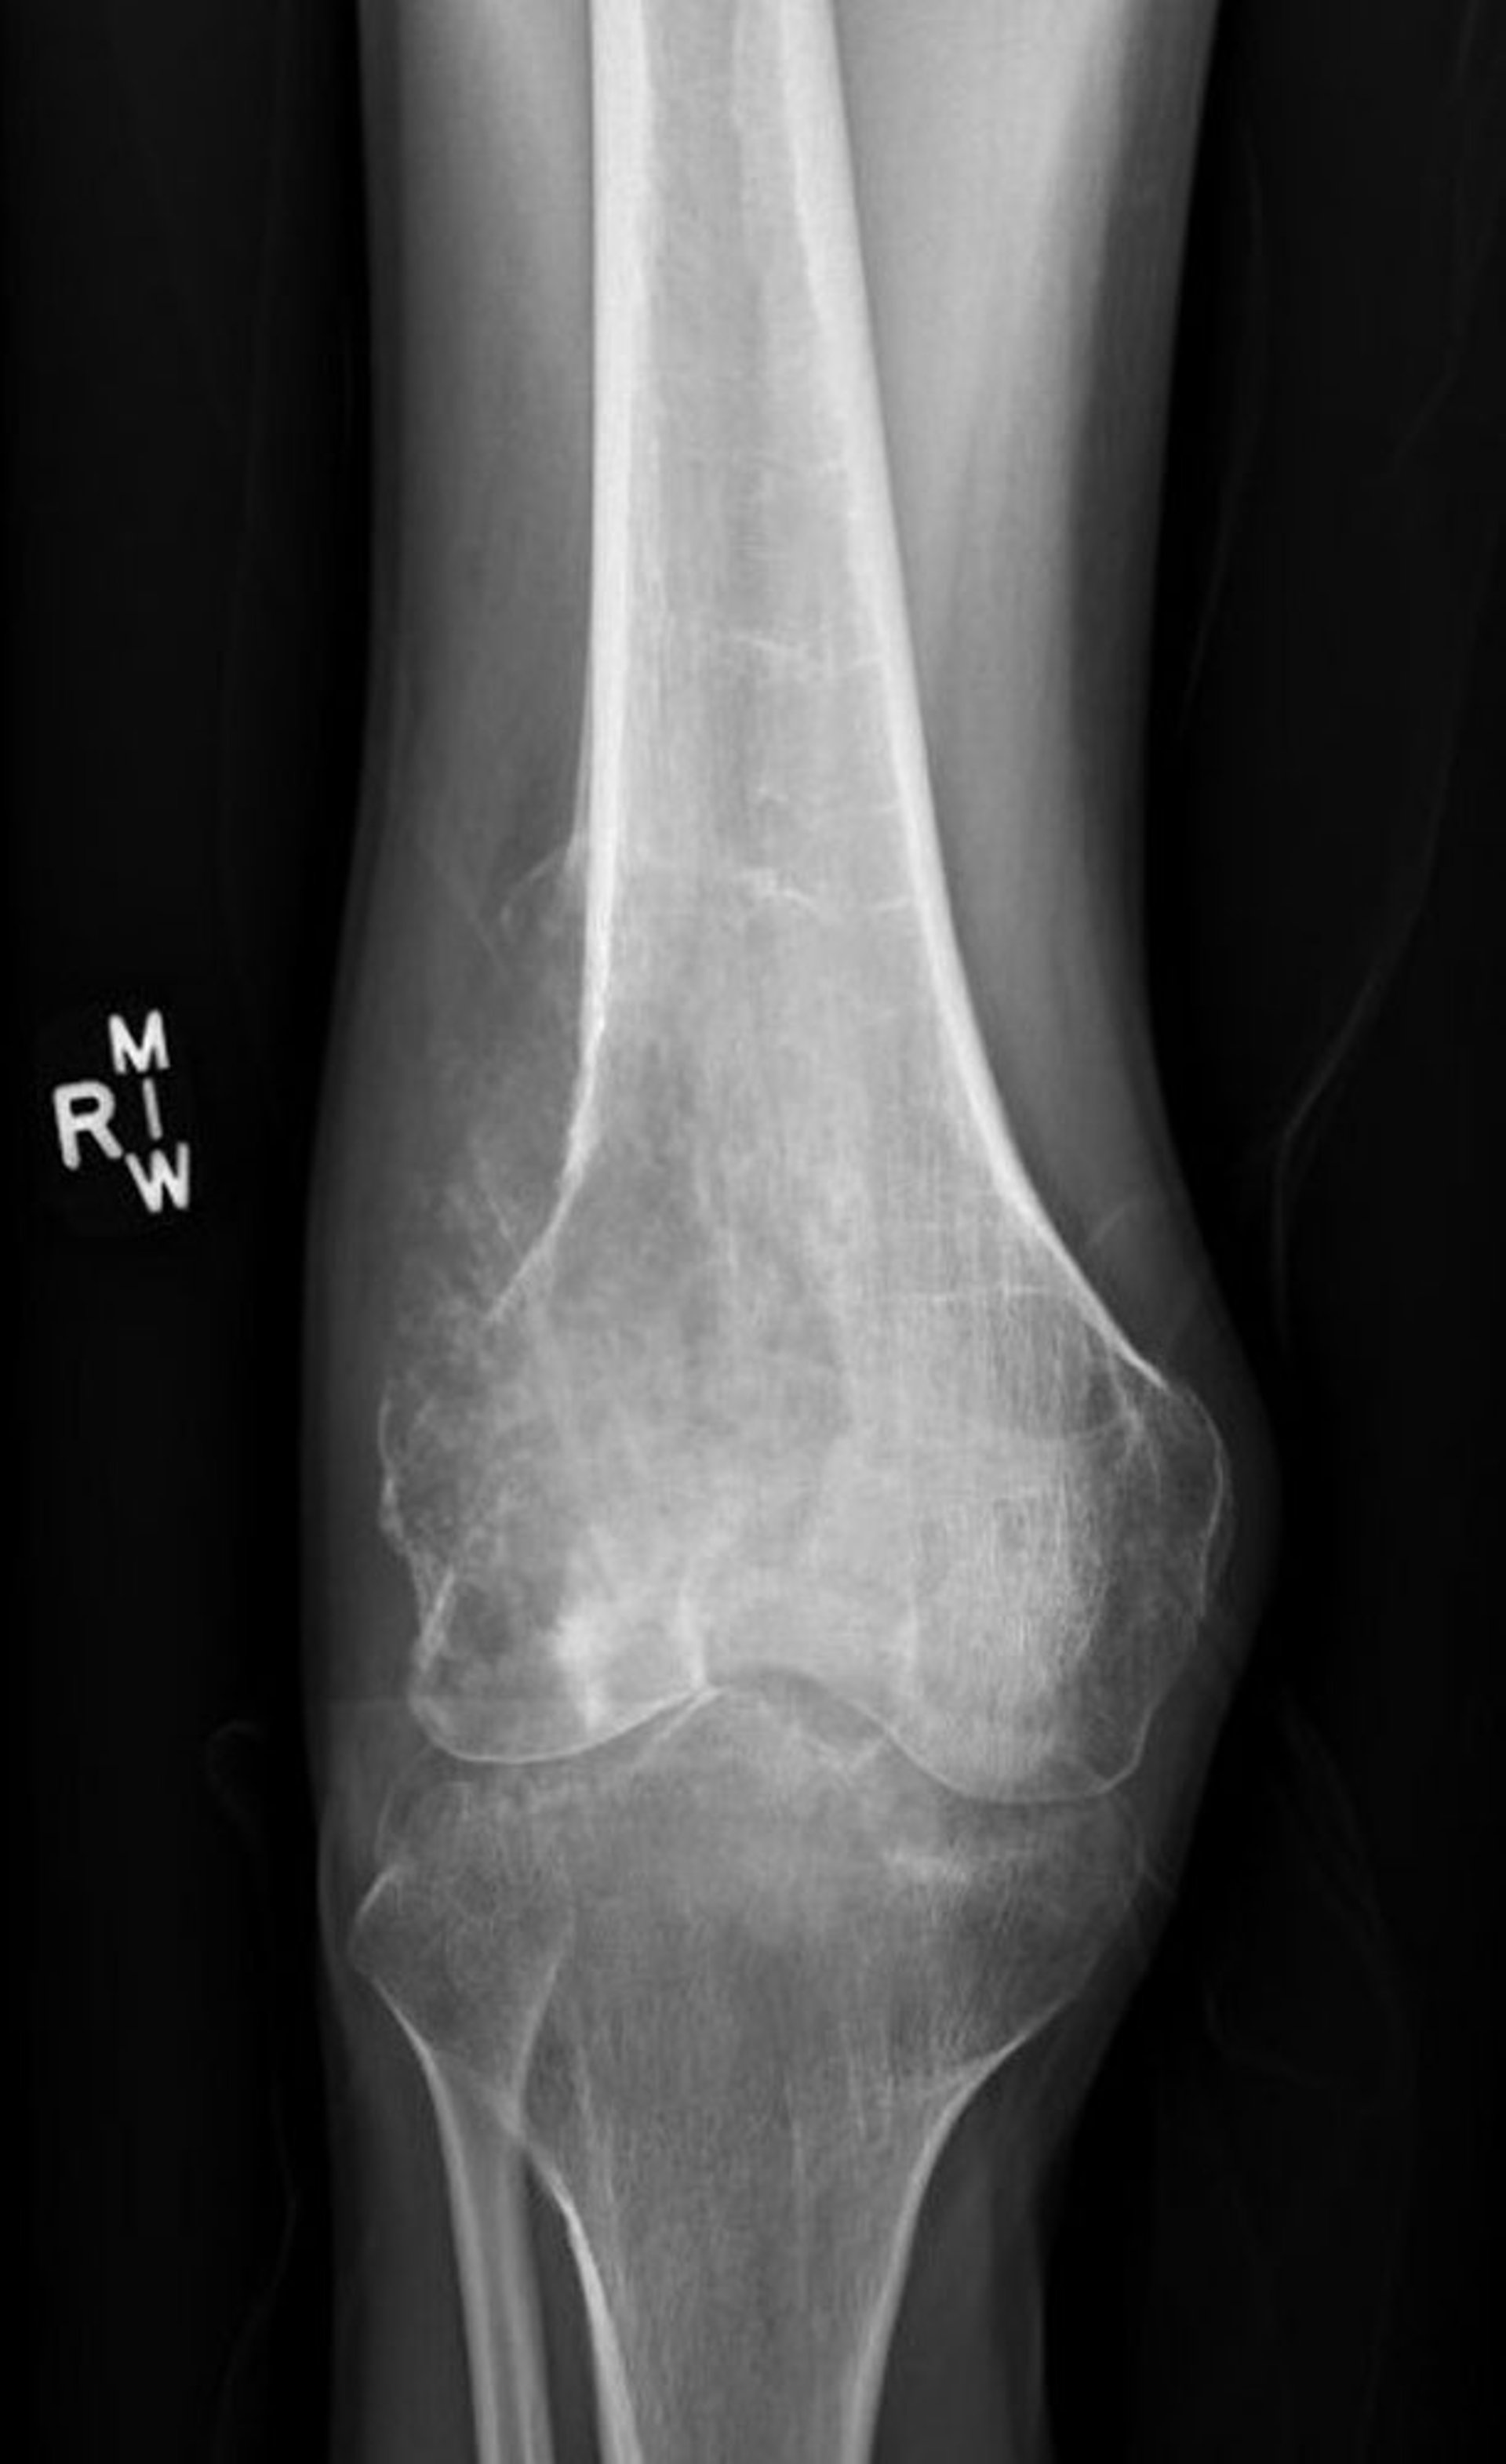

This radiograph of the knee shows a destructive osteosarcoma in the femur above the knee with a lytic destructive appearance and a classic Codman's triangle showing pathologic periosteal elevation.

Image courtesy of Lukas Nystrom, MD.